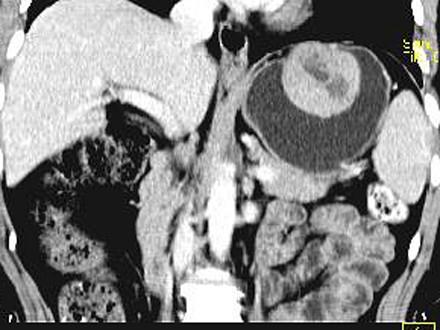

问题 女,51岁,上腹部隐痛不适,CT检查如图,可能的诊断是 ( )

选项 A、胃溃疡 B、胃间质瘤 C、胃息肉 D、胃腺瘤 E、胃癌

答案 B